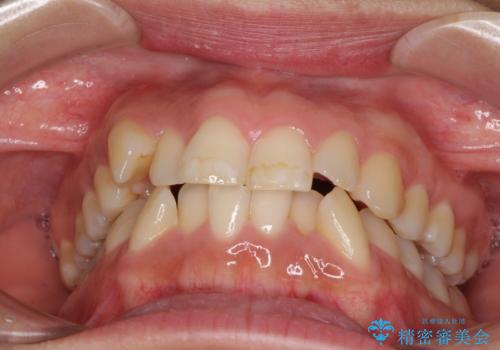

- 上下前歯のデコボコを気にして来院された患者様です。

デコボコが強いため、非抜歯で矯正をすると出っ歯仕上がりとなるため、上下左右の第一小臼歯4本を抜歯することとしました。